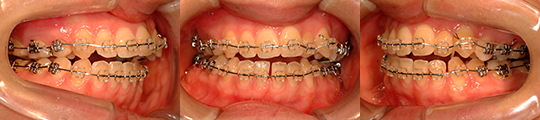

| 治療タイプ | 顎変形症 (保険診療) |

| 性別 | 女性 |

| 治療開始時年齢 | 27才10か月 |

| 診断名 | 他院での矯正治療の既往がある 上顎咬合平面の右上がり傾斜と 下顎骨右方偏位を呈する 開咬を伴う顔面非対称 |

| 使用装置 | 上下顎マルチブラケット矯正装置 |

| 抜歯or非抜歯 | 非抜歯 |

| 抜歯部位 | 上顎右側:(第一小臼歯既抜) 下顎右側:(第三大臼歯) 下顎左側:(第一小臼歯既抜) |

| 顎矯正手術術式 | 術前矯正治療を行わずに、 上顎Le Fort T型骨切り術 (LF-T : Le Fort T osteotomy) 両側下顎枝垂直骨切り術 (IVRO : Intraoral vertical ramus osteotomy) |

| 手術時年齢 | 27才10か月 |

| 治療期間 | 術前矯正治療を行わずに、 1年4か月(マルチブラケット装置装着期間) 装置装着1か月後に手術 術後1か月半より治療開始 |